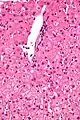

Micrograph showing ground glass hepatocytes. H&E stain.

In liver pathology, a ground glass hepatocyte, abbreviated GGH, is a liver parenchymal cell with a flat hazy and uniformly dull appearing cytoplasm on light microscopy. The cytoplasm's granular homogeneous eosinophilic staining is caused by the presence of HBsAg.

The appearance is classically associated with abundant hepatitis B antigen in the endoplasmic reticulum, but may also be drug-induced.[1][2] In the context of hepatitis B, GGHs are only seen in chronic infections, i.e. they are not seen in acute hepatitis B.